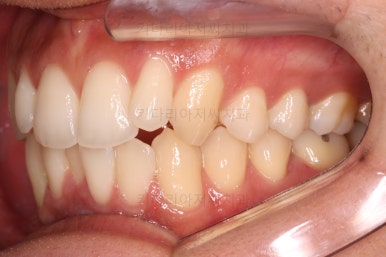

전후 비교해 보겠습니다.

교합이나 가지런한 느낌 매우 좋아졌고요.

특히 옆 라인에서도 둥글었던 윗입술도 오목한 곡선이 생기면서 돌출감이 좋아졌고 턱끝의 윤곽도 생기면서 무턱 느낌도 좋아졌습니다.

윗니의 위치를 보면 처음은 아랫입술에 가려질 정도로 아래로 내려와 있었는데 치료 후에는 앞니가 보이는 정도로 위치 조절이 잘 되었네요.

발치 없이도 문제점과 개선방향을 잘 셋팅한다면 이렇게 좋은 결과를 만들어낼 수 있답니다.